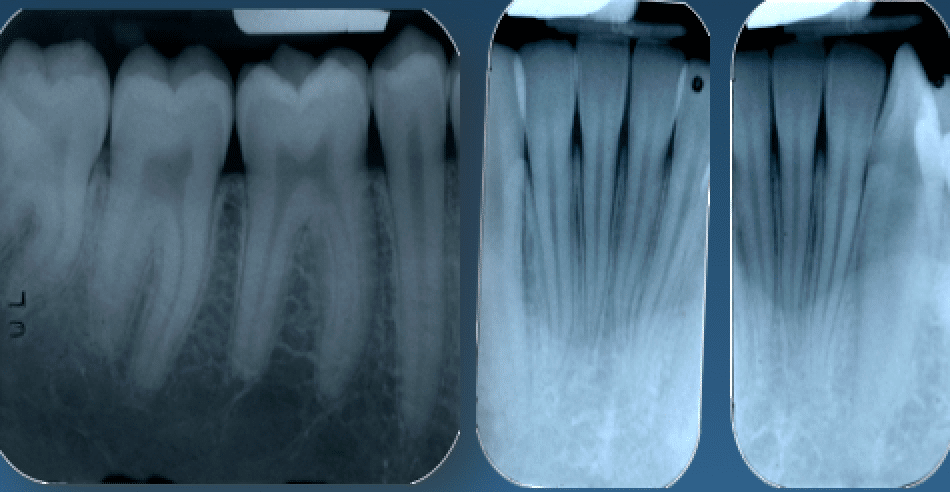

Questo importante esame deve essere sempre e comunque validato da radiografie endorali (non ortopantomografia), essenziali per potersi avvicinare quanto più possibile alla verità clinica.

Ho mal di denti cosa fare Prof. Checchi Bologna

Radiografie endorali

Quante volte i pazienti mi hanno chiesto di non fare radiografie, non capendo che esse permettono numerose considerazioni che, insieme all’esame clinico parodontale del sondaggio, porteranno ad un piano di trattamento con o senza chirurgie, con o senza estrazioni, con più o con meno costi? Vi sembra poco tutto questo?